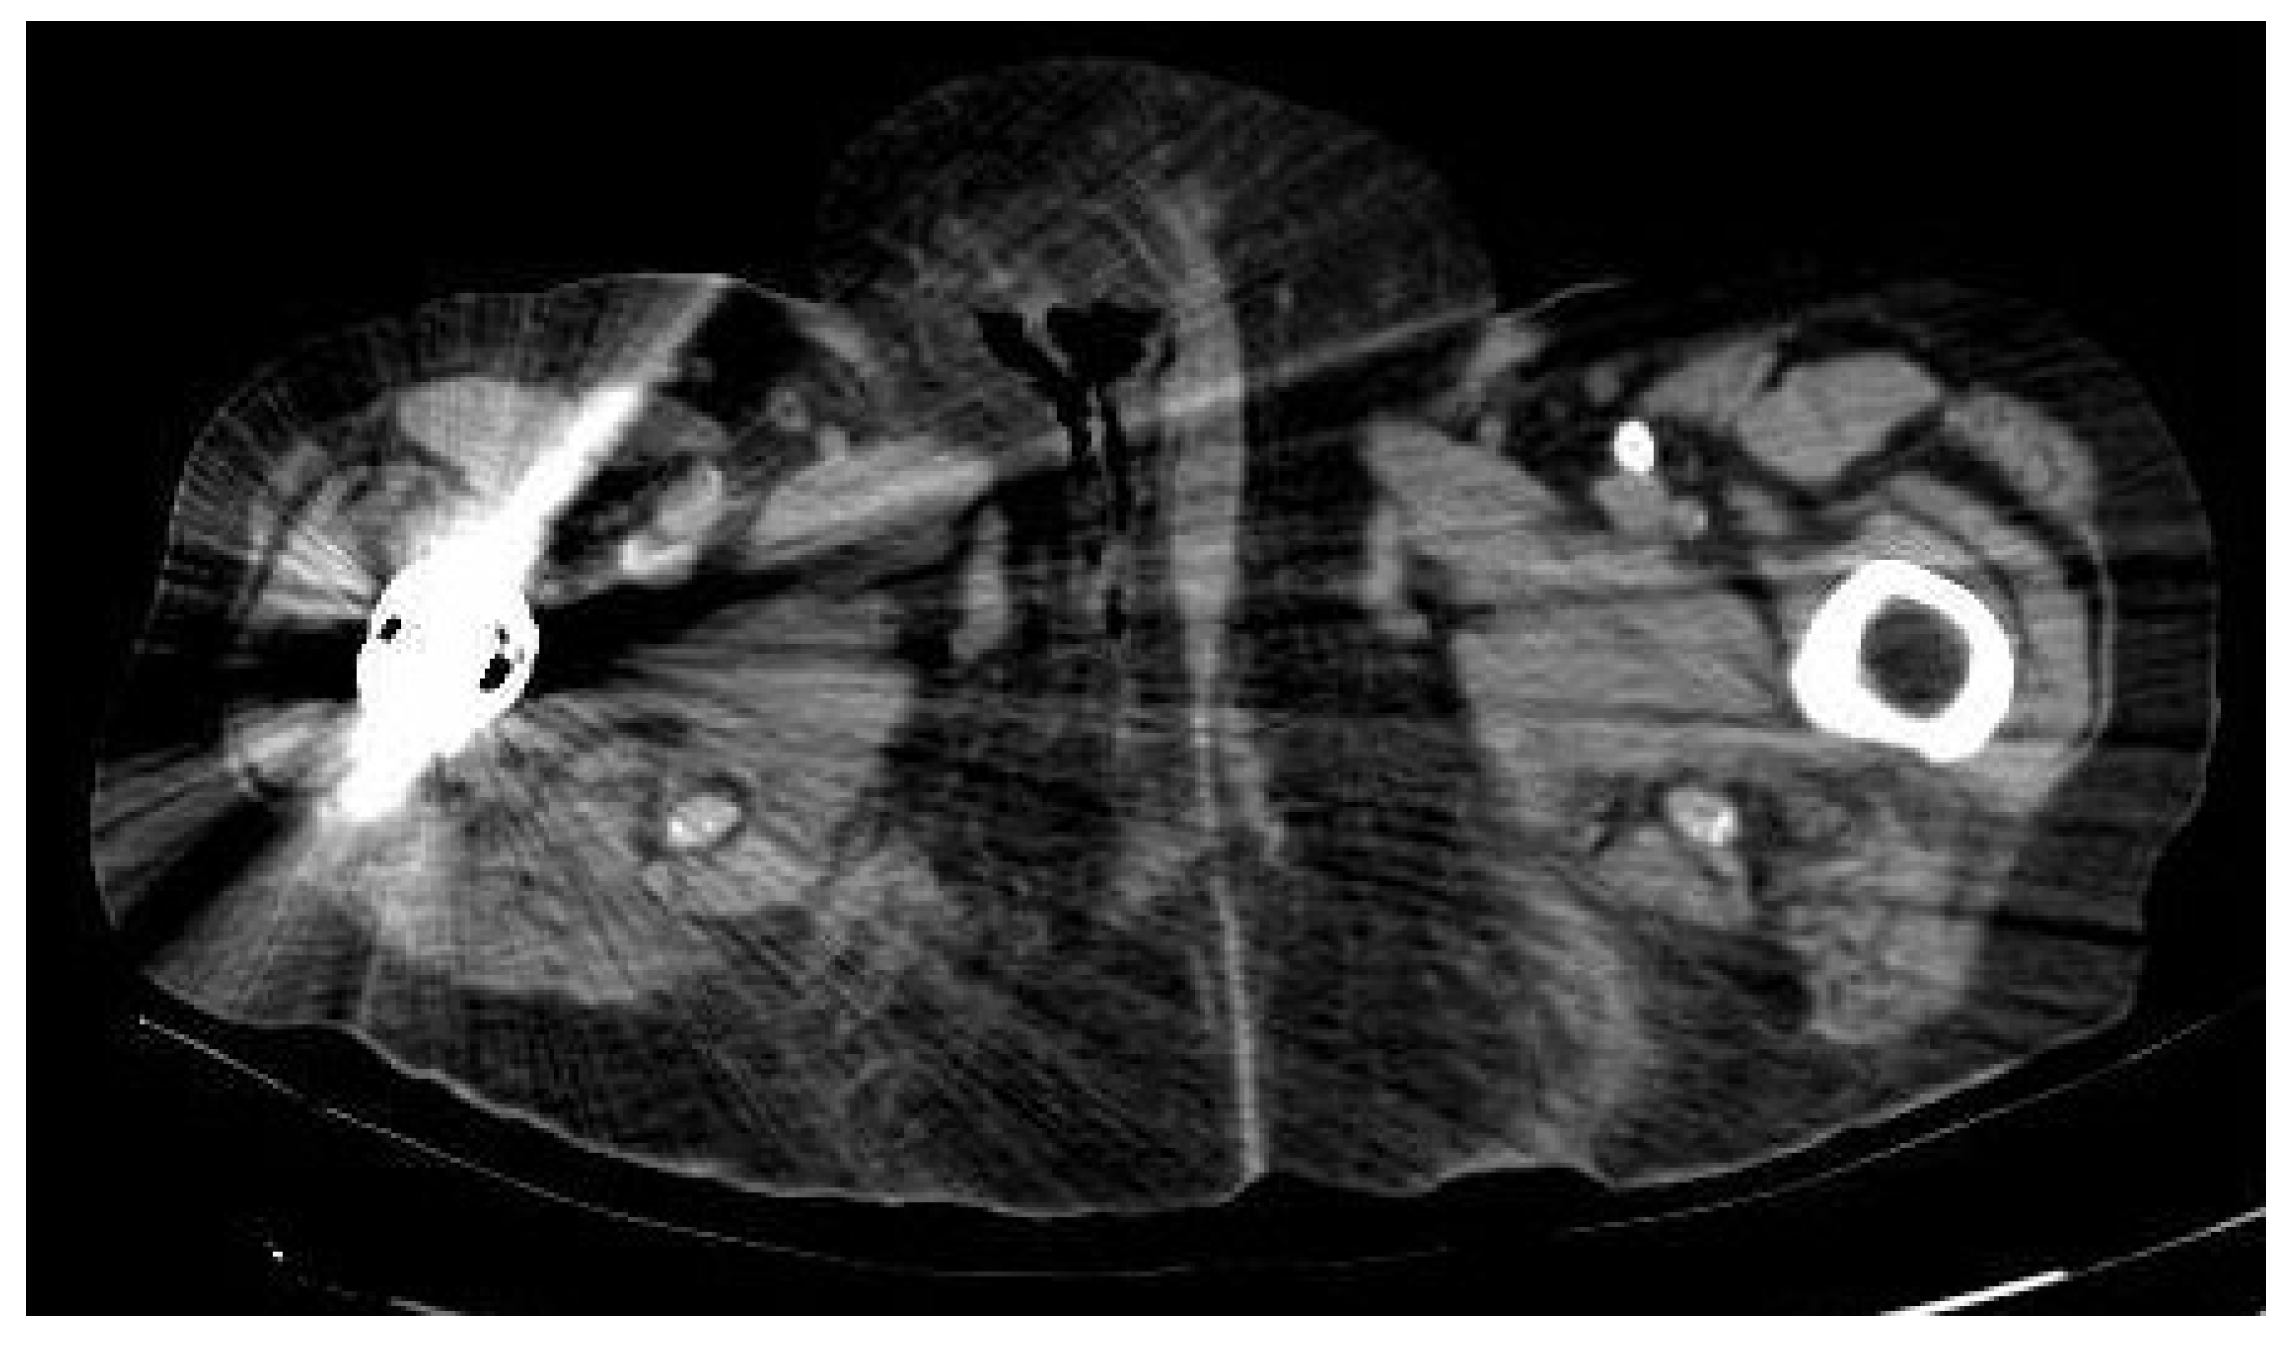

On the initial scan, her general condition was fair. She had blood pressure around 122/52 mmHg, HR 110 bpm and 36 °C of temperature. Right labia majora was enlarged, indurated and erythematous. Additionally, she had a painful ulcer in the lower third. Blood tests revealed hemoglobin 8.9 g/dl, platelets 426,000/L, leukocytosis 37,640/L with 90% neutrophils and RCP of 285 mg/dl. Glycemia at 465 mg/dl. No more unaltered parameters were associated. A CT of the abdomen and pelvis showed subcutaneous edema and air in the perineal area and right vulvar area extending into the presacral soft tissues suggestive of FG (Figure 3).

Figure 3.

CT of the abdomen and pelvis showed subcutaneous edema and air inside the soft tissues of the genital area extending into the presacral soft tissues of FG. The hip replacement slightly distorts the image.